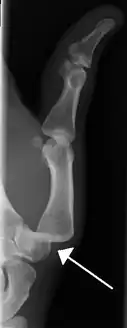

- Radiograph of right fifth phalanx bone dislocation

- Radiograph of left index finger dislocation